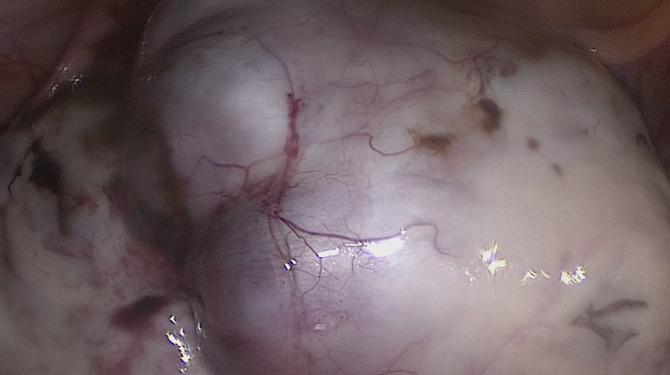

Laparoscopy

• The camera transmits an image of the organs inside the abdomen onto a television monitor. The surgeon is not able to see directly into the patient without the traditional large incision. The video camera becomes a surgeon’s eyes in laparoscopy surgery, since the surgeon uses the image from the video camera positioned inside the patient’s body to perform the procedure.